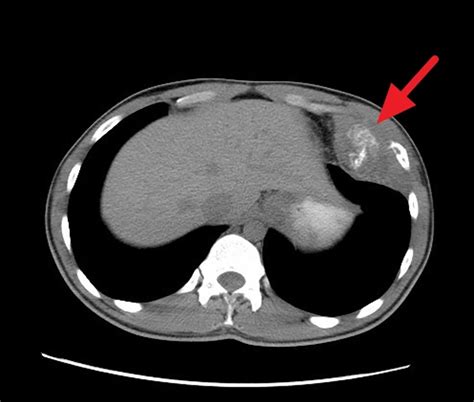

• Extent of Disease at Diagnosis: This is arguably the most significant factor. Patients with localized disease (cancer confined to the primary site) generally have a better prognosis than those with metastatic disease (cancer that has spread to distant sites like the lungs, bones, or bone marrow).

Metastatic Cancer has spread to distant organs or tissues. More challenging; requires intensive treatment.

Improving the Ewing sarcoma prognosis relies heavily on a multimodal treatment approach. Because Ewing sarcoma is a systemic disease, local treatments alone are rarely sufficient. Instead, a combination of systemic chemotherapy, surgical intervention, and radiation therapy is typically required to maximize the chances of long-term survival.